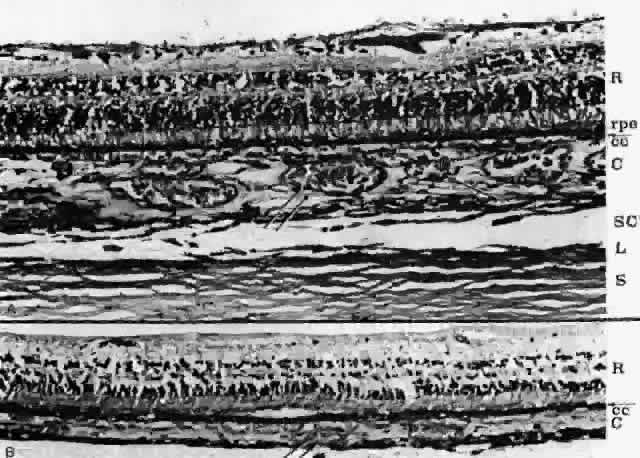

BRUCH'S MEMBRANE Bruch's membrane, also called the lamina vitrea, is the inner layer

of the choroid. This thin, acellular, well-delineated zone between the

retina and choroid extends from the optic nerve to the ora serrata. Composed

of elements from both the retina and the choroid, Bruch's

membrane is an integral part of the choroid. From internal to external, the

membrane is formed of five layers: the basement membrane of the RPE, the inner collagenous zone, the elastic tissue layer, the outer collagenous zone, and the basement membrane of the choriocapillaris (Fig. 8).  Fig. 8. Bruch's membrane. Basement membrane of retinal pigment epithelium (rbm), inner collagenous zone (ic), elastic tissue layer (etl), outer collagenous zone (oc) and basement membrane of choriocapillaris (cbm). (× 14,500) Fig. 8. Bruch's membrane. Basement membrane of retinal pigment epithelium (rbm), inner collagenous zone (ic), elastic tissue layer (etl), outer collagenous zone (oc) and basement membrane of choriocapillaris (cbm). (× 14,500)

Bruch's membrane is thickest near the optic disc, measuring 2 to 4 μm, and

gradually decreases in thickness to 1 to 2 μm peripherally.16 The innermost layer, the basement membrane of the RPE, is a continuous

membrane measuring 0.3 μm thick. The outer layer, the basement membrane

of the choriocapillaris, is 0.14 μm thick and is discontinuous

at the intercapillary septa. The inner and outer collagenous layers

are continuous and measure 1.5 μm and 0.14 μm, respectively. The

middle elastic tissue layer is discontinuous. Normally, the layers of

Bruch's membrane are so closely interwoven that they cannot be separated